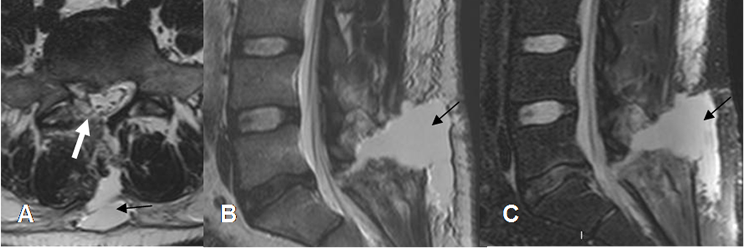

Fig 202. Cambios tratamiento.

A: TAC reconstrucción sagital, B: TAC axial y C: RM axial en T2. Lesión lítica vertebral, por mieloma.

Fig 203. Cambios tratamiento.

A: Rx AP, B: RM axial en T1 y C: RM sagital en T1. Igual paciente anterior. Vertebroplastia con cemento, encontrado como imagen densa en la Rx e hipointensa en la RM.